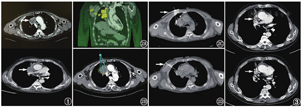

患者男,65岁,2017年1月因咳嗽等不适就诊于本院,诊断为右肺癌(穿刺病理及免疫组织化学检测结果倾向于肉瘤样癌);行4周期紫杉醇脂质体+卡铂化疗,复查CT示局部进展,后行体部伽马刀治疗(35 Gy/14次);2017年6月再次就诊,疗效评价为部分缓解,行2周期表柔比星+达卡巴嗪治疗,未规律复查。后患者因"半年前出现咳嗽、咳血痰,胸部CT示肿瘤进展"于2019年5月行氩氦刀治疗,并行局部放射治疗(共28 Gy/7次),症状逐渐平稳。2019年9月患者因"1周前出现颜面部及上肢肿胀,并伴有咳嗽、咳痰,胸闷、喘憋,症状逐渐加重"就诊。体格检查:颜面部、颈部红肿明显,颈静脉怒张,双上肢肿胀,前胸壁及上腹部浅表静脉曲张;双肺叩诊过清音,未闻及干湿性啰音,右肺呼吸音稍低。胸部增强CT示:右肺上叶占位,大小约49 mm×59 mm×81 mm,侵犯上腔静脉(图1);肺气肿;纵隔内多发扩张血管;双侧肾上腺转移不除外。基因检测示:表皮生长因子受体(epidermal growth factor receptor, EGFR)突变、间变性淋巴瘤激酶(anaplastic lymphoma kinase, ALK)基因融合均为阴性。肿瘤标志物细胞角蛋白19片段、鳞状细胞癌相关抗原、神经元特异性烯醇化酶均正常。血气分析:氧分压77.1 mmHg (1 mmHg=0.133 kPa),二氧化碳分压38.9 mmHg。诊断:(1)右肺肉瘤样癌(pulmonary sarcomatoid carcinoma, PSC)放化疗后,上腔静脉综合征,双侧肾上腺转移不除外;(2)双肺肺气肿。患者行三维(three-dimensional, 3D)打印模板联合CT引导125I粒子植入术,手术过程严格按照CT联合模板引导放射性粒子植入治疗肺癌技术流程进行[1]。术前将胸部强化CT导入治疗计划系统,勾画肿瘤靶区,设计针道及载入粒子,设计3D模板。术中固定患者体位,麻醉,3D模板复位后,插入植入针,待所有植入针到达预定位置后按术前计划植入粒子。患者手术过程顺利,共植入22.2 MBq粒子103颗,术后即刻90%大体肿瘤体积接受剂量(dose delivered to 90% gross tumor volume, D90)=102.89 Gy(图2)。术后患者出现血气胸,给予胸腔闭式引流,1周后拔管。患者症状明显好转,术后2个月肿瘤体积缩小(图3),术后6个月因肿瘤全身进展、肺部感染、呼吸衰竭死亡。